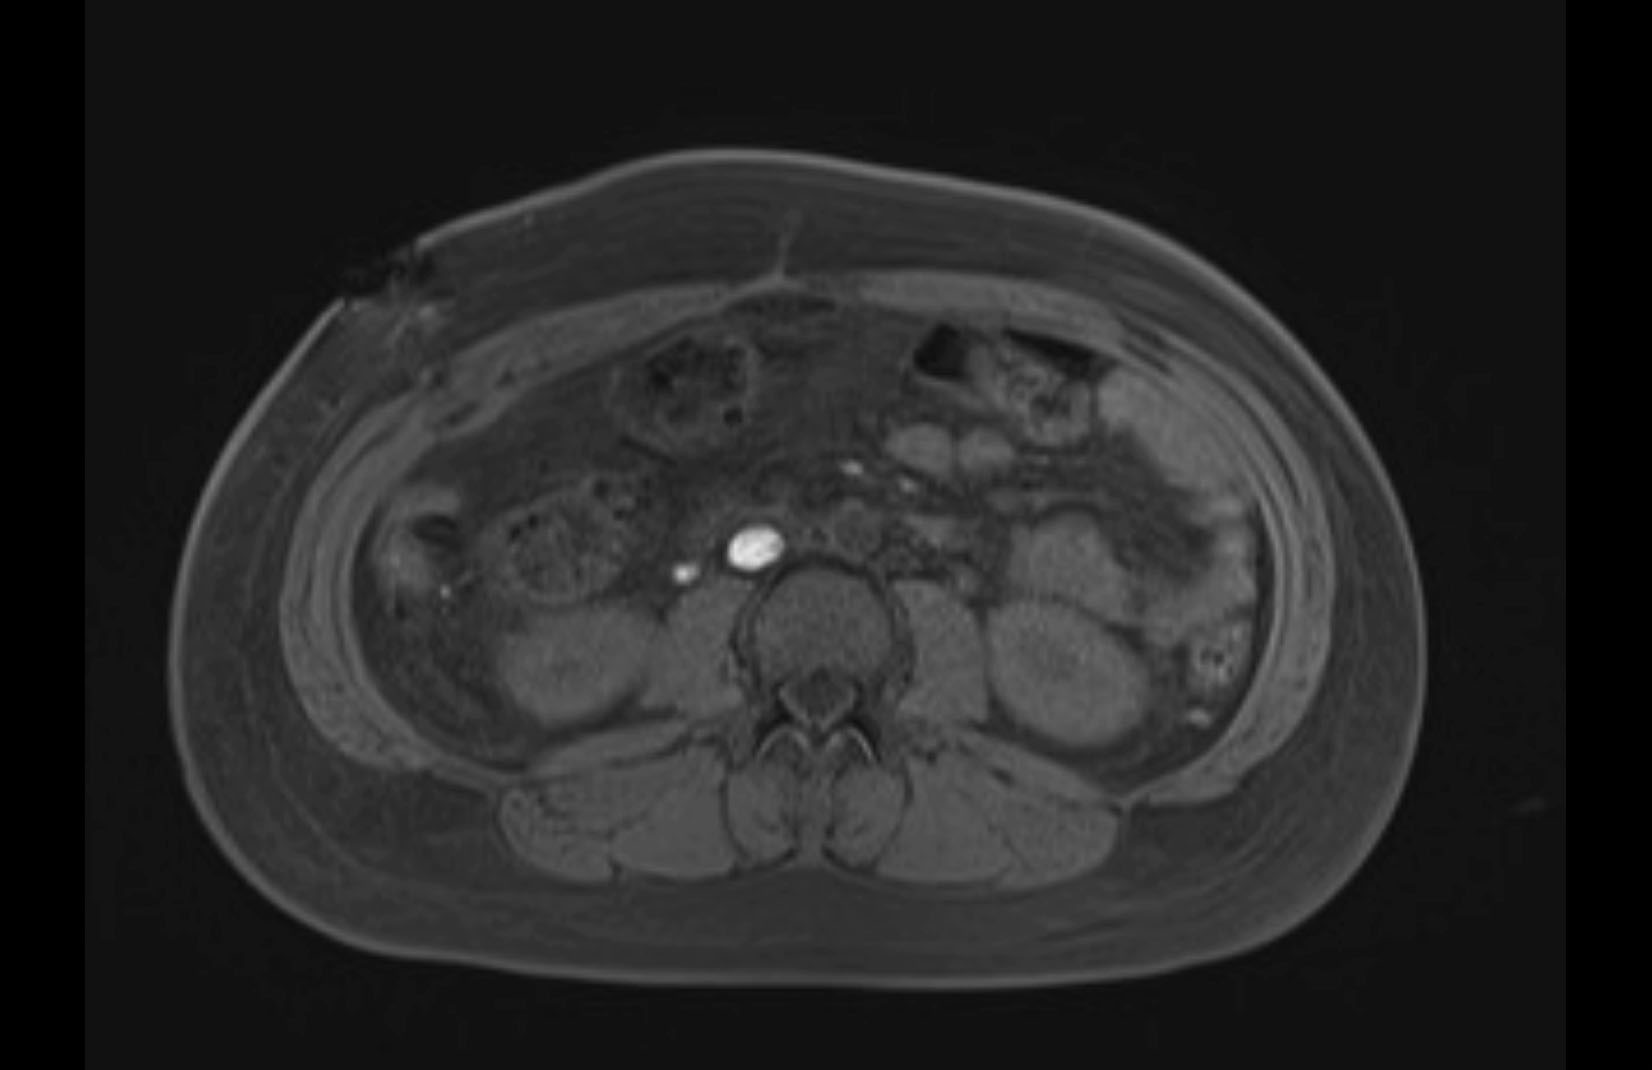

Imaging Analysis

Look through the patient's CT scan to identify any areas of concern for the necessary procedure.

MRI T1

MRI T2

Based on initial findings, which issue(s) would you be most concerned about?